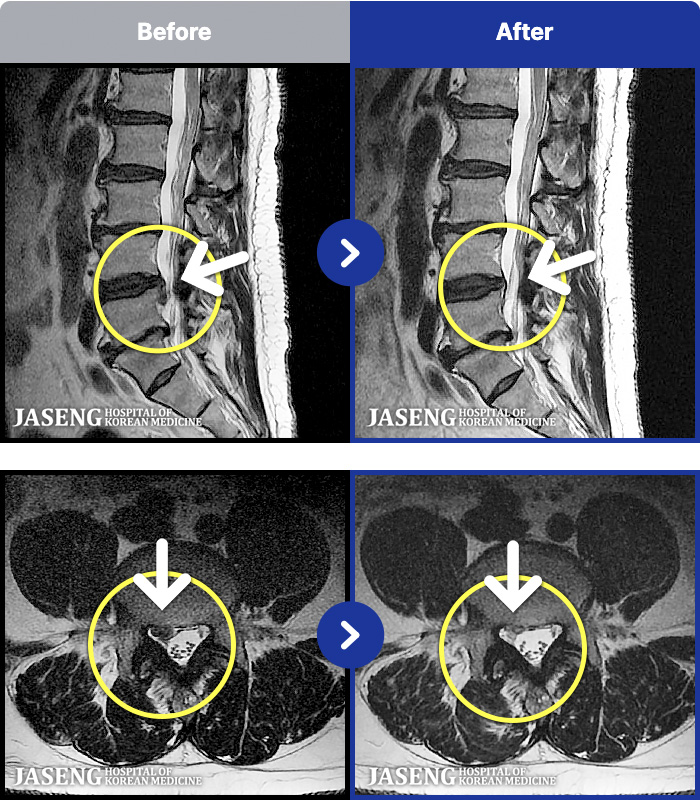

[ϻ] 24.07.25~25.08.01

ȯںп Ǹ ǿ ԿǾ, ο ġ ۿ Ƿ ġḦ Ͻñ ٶϴ.